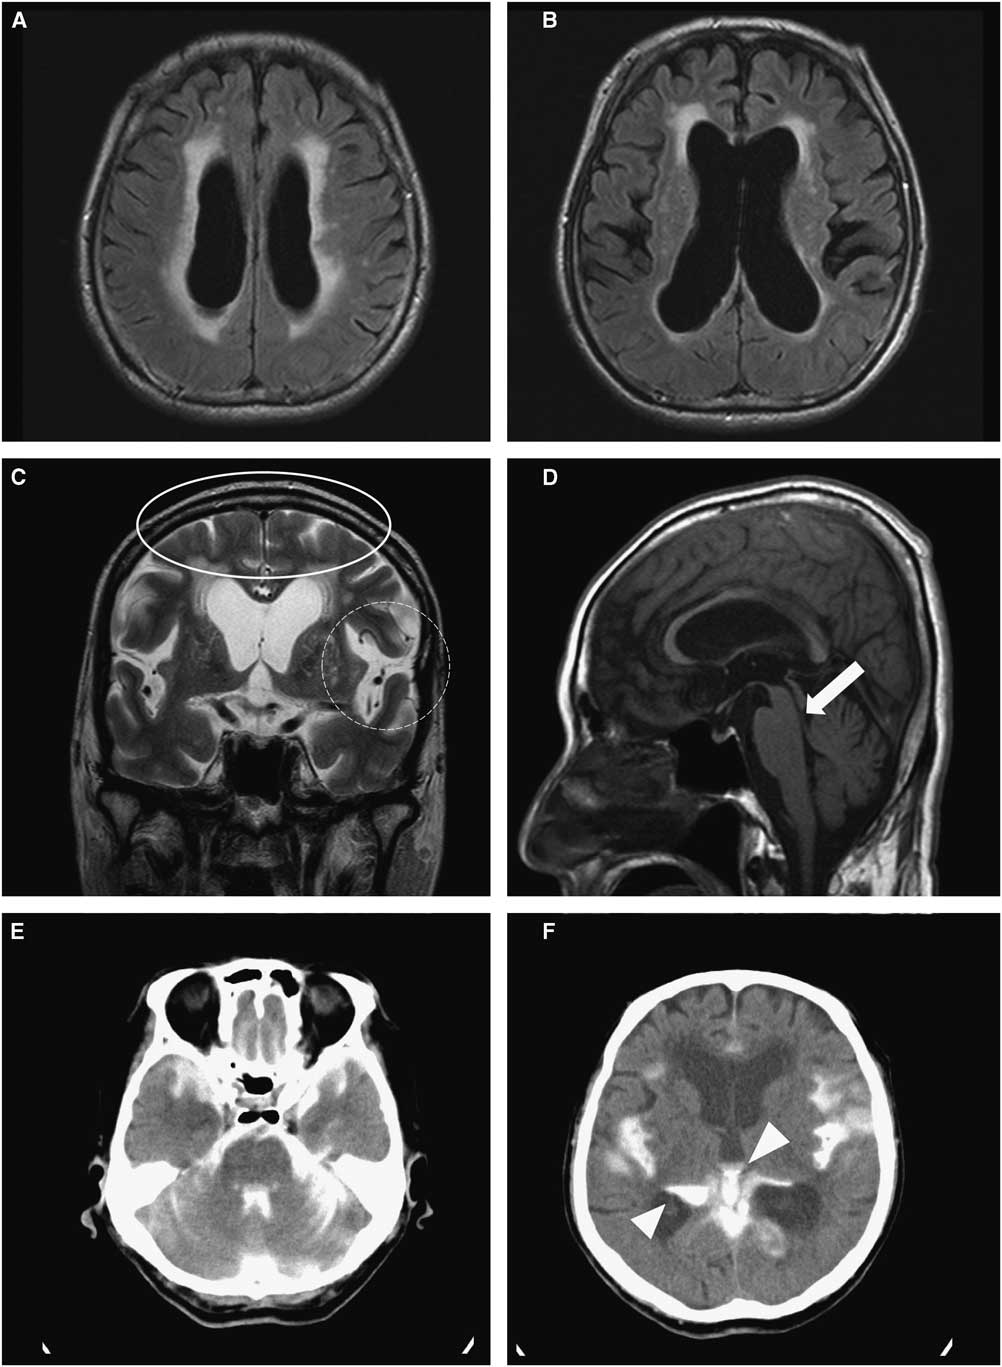

A 1.5-T brain MRI revealed not only enlargement of the lateral ventricles, but also a periventricular hyperintensity in contact with the lateral ventricles in axial fluid attenuated inversion recovery (FLAIR) images (Figures 1A and B). The Evans’ index was 0.35, indicating hydrocephalus. Coronal T2-weighted images featured enlarged ventricles; tight, high-convexity, and medial surface subarachnoid spaces; and a bilaterally expanded Sylvian fissure (Figure 1C), suggesting disproportionately enlarged subarachnoid-space hydrocephalus (DESH).Reference Hashimoto, Ishikawa, Mori and Kuwana 3 , Reference Virhammar, Laurell, Cesarini and Larsson 4 T1 sagittal images revealed AS without any obstructive lesion (Figure 1D).

Figure 1 Brain MRI and CT cisternography of the patient revealing hydrocephalus with idiopathic aqueductal stenosis: (A & B) Enlargement of lateral ventricles and periventricular hyperintensity regarded as interstitial edema. (C) Narrow medial sulci (oval ring) and bilaterally dilated Sylvian fissure (dotted round ring), indicating disproportionately enlarged subarachnoid-space hydrocephalus (DESH). (D) Aqueductal stenosis with no obstructive mass or lesion (white arrow). (E & F) CT cisternography five hours after lumbar introduction of metrizamide, showing filling of the fourth ventricle as well as the Sylvian fissure and only a partial filling in the third and lateral ventricles (white arrow heads).

We performed brain metrizamide dynamic CT cisternography on the patient. Five hours later CT cisternography showed a full filling of the fourth ventricle (Figure 1E) but only a small filling of the third and lateral ventricles (Figure 1F), indicating a partial obstruction of AS-associated hydrocephalus. The patient’s gait difficulty was considerably improved after draining approximately 30 cc of cerebrospinal fluid (CSF) from the lumbar cistern; opening pressure at the lumbar puncture was 16 cmH2O. Since the patient responded moderately to CSF drainage, a ventriculoperitoneal (VP) shunt was applied. After the VP shunt operation, the patient’s PAGF symptoms were notably improved without any medication (Video 2). He improved until about two months later, when he died suddenly from an unknown cause.

Idiopathic AS is generally regarded as one of the important etiologies of obstructive hydrocephalus.Reference Zeidler, Dorman, Ferguson and Bateman 5 In our case, however, metrizamide CT cisternography demonstrated an incomplete type of obstructive hydrocephalus, as previously described (Figures 1E and F). Furthermore, the MRI findings were compatible with DESH (Figure 1C), a characteristic feature of idiopathic normal pressure hydrocephalus.Reference Hashimoto, Ishikawa, Mori and Kuwana 3 , Reference Virhammar, Laurell, Cesarini and Larsson 4 In line with our findings, Rodis et al. stated that most cases of late-onset AS resembled typical signs and symptoms of normal pressure hydrocephalus.Reference Rodis, Mahr, Fehrenbach, Meixensberger, Merkenschlager and Bernhard 1 Therefore, our case may indicate that adult chronic AS-associated hydrocephalus could be a transitional status between obstructive and normal-pressure hydrocephalus. It is reasonable to infer a common mechanism between idiopathic normal-pressure hydrocephalus and an incomplete type of obstructive hydrocephalus; some communicating portion of aqueductal stenosis might be responsible for the pathophysiology. In addition, we supposed that was the reason why the patient showed the improvement of gait difficulty after CSF drainage with the lumbar puncture.